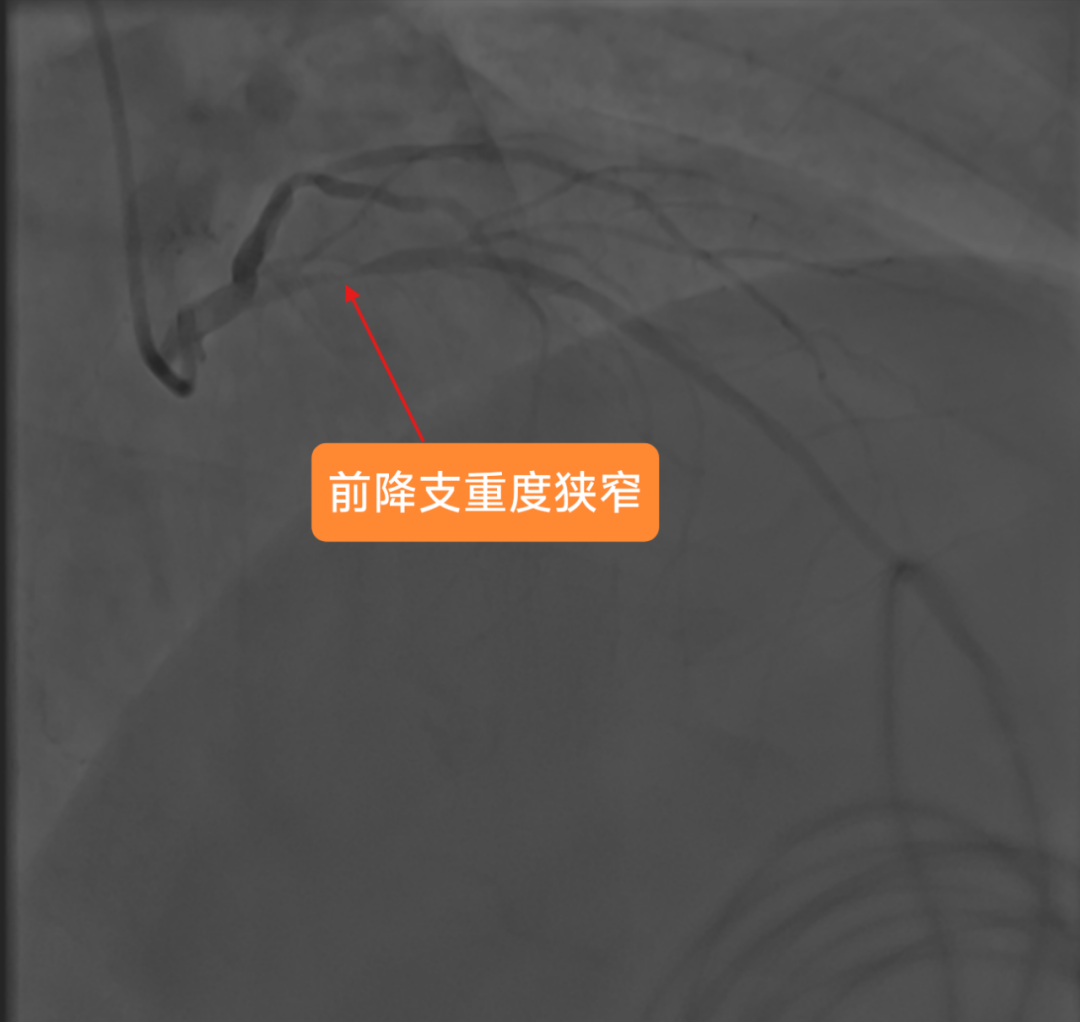

2025年3月4日手术当天,医生穿刺患者右桡动脉进行造影时,一场危象毫无征兆地出现:患者前降支血管近段狭窄达99%,血管近乎完全闭塞。这意味着心脏随时面临因严重缺血而停跳的危险,大脑也承受着巨大且不可逆的缺血性损伤风险,情况刻不容缓,必须立即进行紧急手术,这是挽救患者生命的关键。

冠脉造影显示患者前降支血管重度狭窄